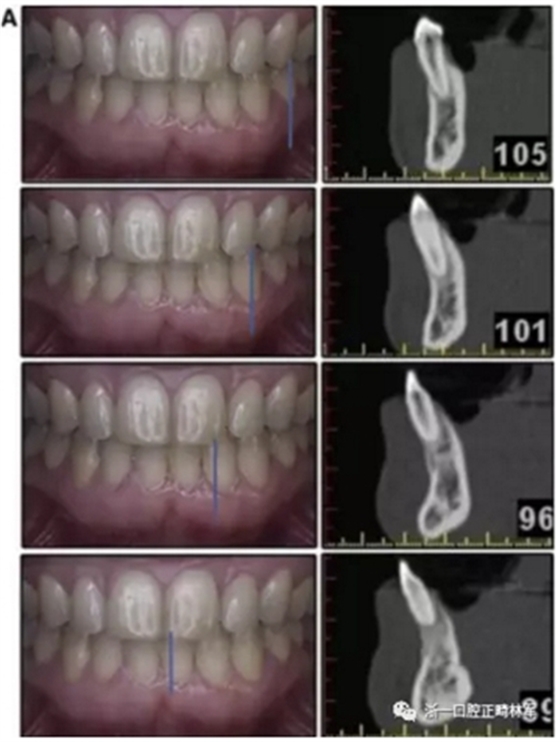

患者決定采用非手術(shù)治療方法,側(cè)貌沒(méi)有任何預(yù)期的變化。治療后面部照片(圖5)顯示她改善的微笑和側(cè)貌,包括尖牙保護(hù)合。由于先天性第一前磨牙缺失,右磨牙關(guān)系為III類。治療后牙齒石膏模型(圖6)顯示實(shí)體牙齒交錯(cuò)排列情況,并且全景X線片顯示可接受的牙根平行度而且沒(méi)有牙根吸收表現(xiàn)(圖7)。最終的頭影測(cè)量片(圖7)證實(shí)了面部評(píng)估,并且描跡圖顯示深覆蓋的改善,同時(shí)保持上頜切牙位置并通過(guò)測(cè)量ANB角度和Wits評(píng)估改善骨性II級(jí)關(guān)系(表)。治療前后的疊加圖顯示由于下頜切牙前傾的增加改善了下唇平衡(圖8)。如相關(guān)治療計(jì)劃所預(yù)測(cè)的那樣,B點(diǎn)出現(xiàn)。A進(jìn)行牙科錐形束計(jì)算機(jī)斷層掃描以記錄下頜前牙區(qū)的骨質(zhì)變化。如預(yù)期的那樣,由于治療導(dǎo)致該區(qū)域的骨量增加(圖9)。